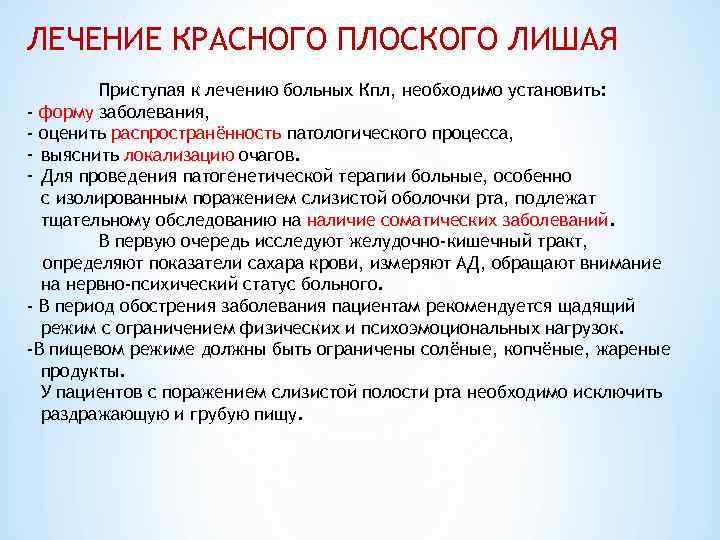

Фото Красного Плоского

Фото Красного Плоского 103 фото